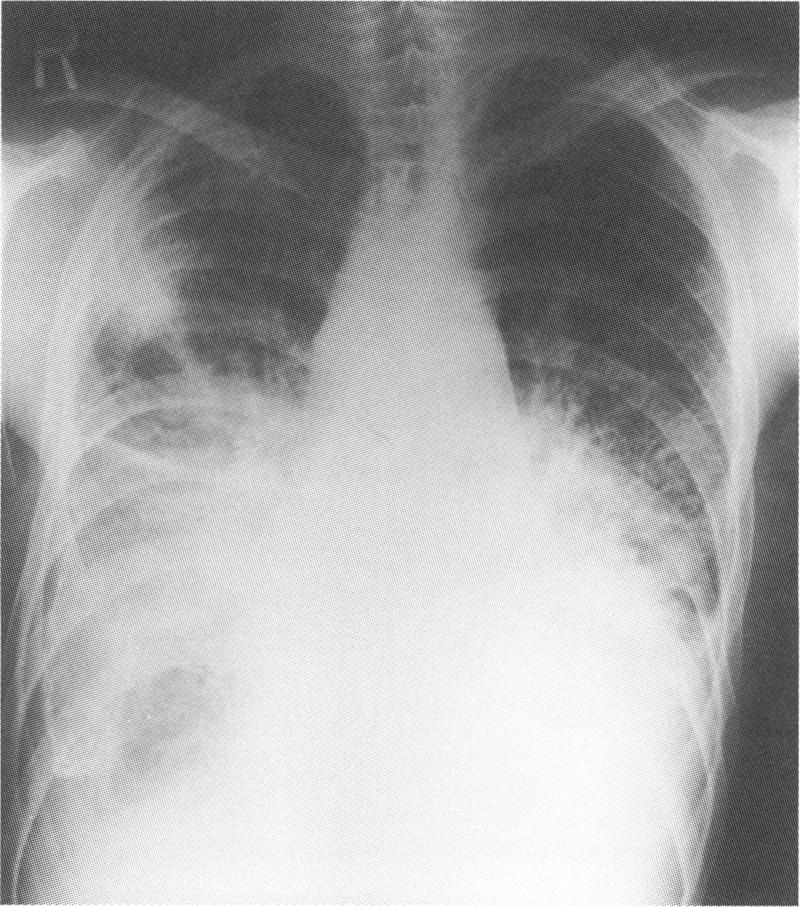

A 25 year old man presented with dyspnoea and was found to have generalised, but predominantly pulmonary, lymphangiectasis without gastrointestinal symptoms. This is an unusual presentation of a disorder previously diagnosed only in childhood.

一名25岁男性因呼吸困难就诊,检查发现患有全身性淋巴管扩张症,以肺部为主,无胃肠道症状。这是一种此前仅在儿童期被诊断出的疾病的不寻常表现。